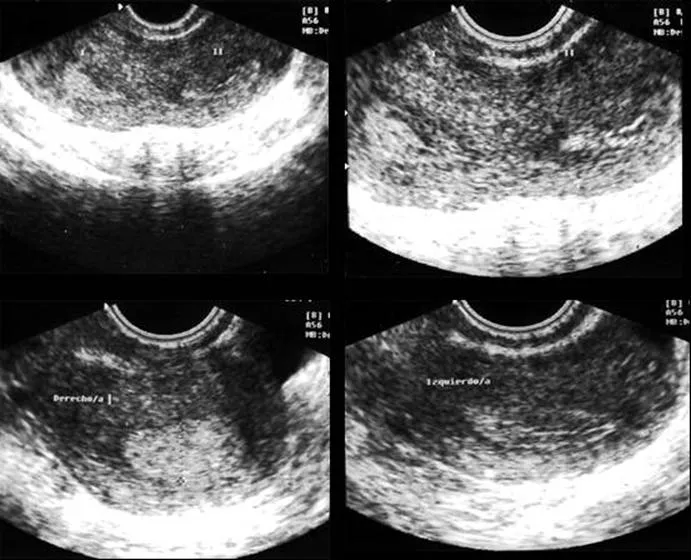

Malformaciones uterinas (página 2) - Monografias.